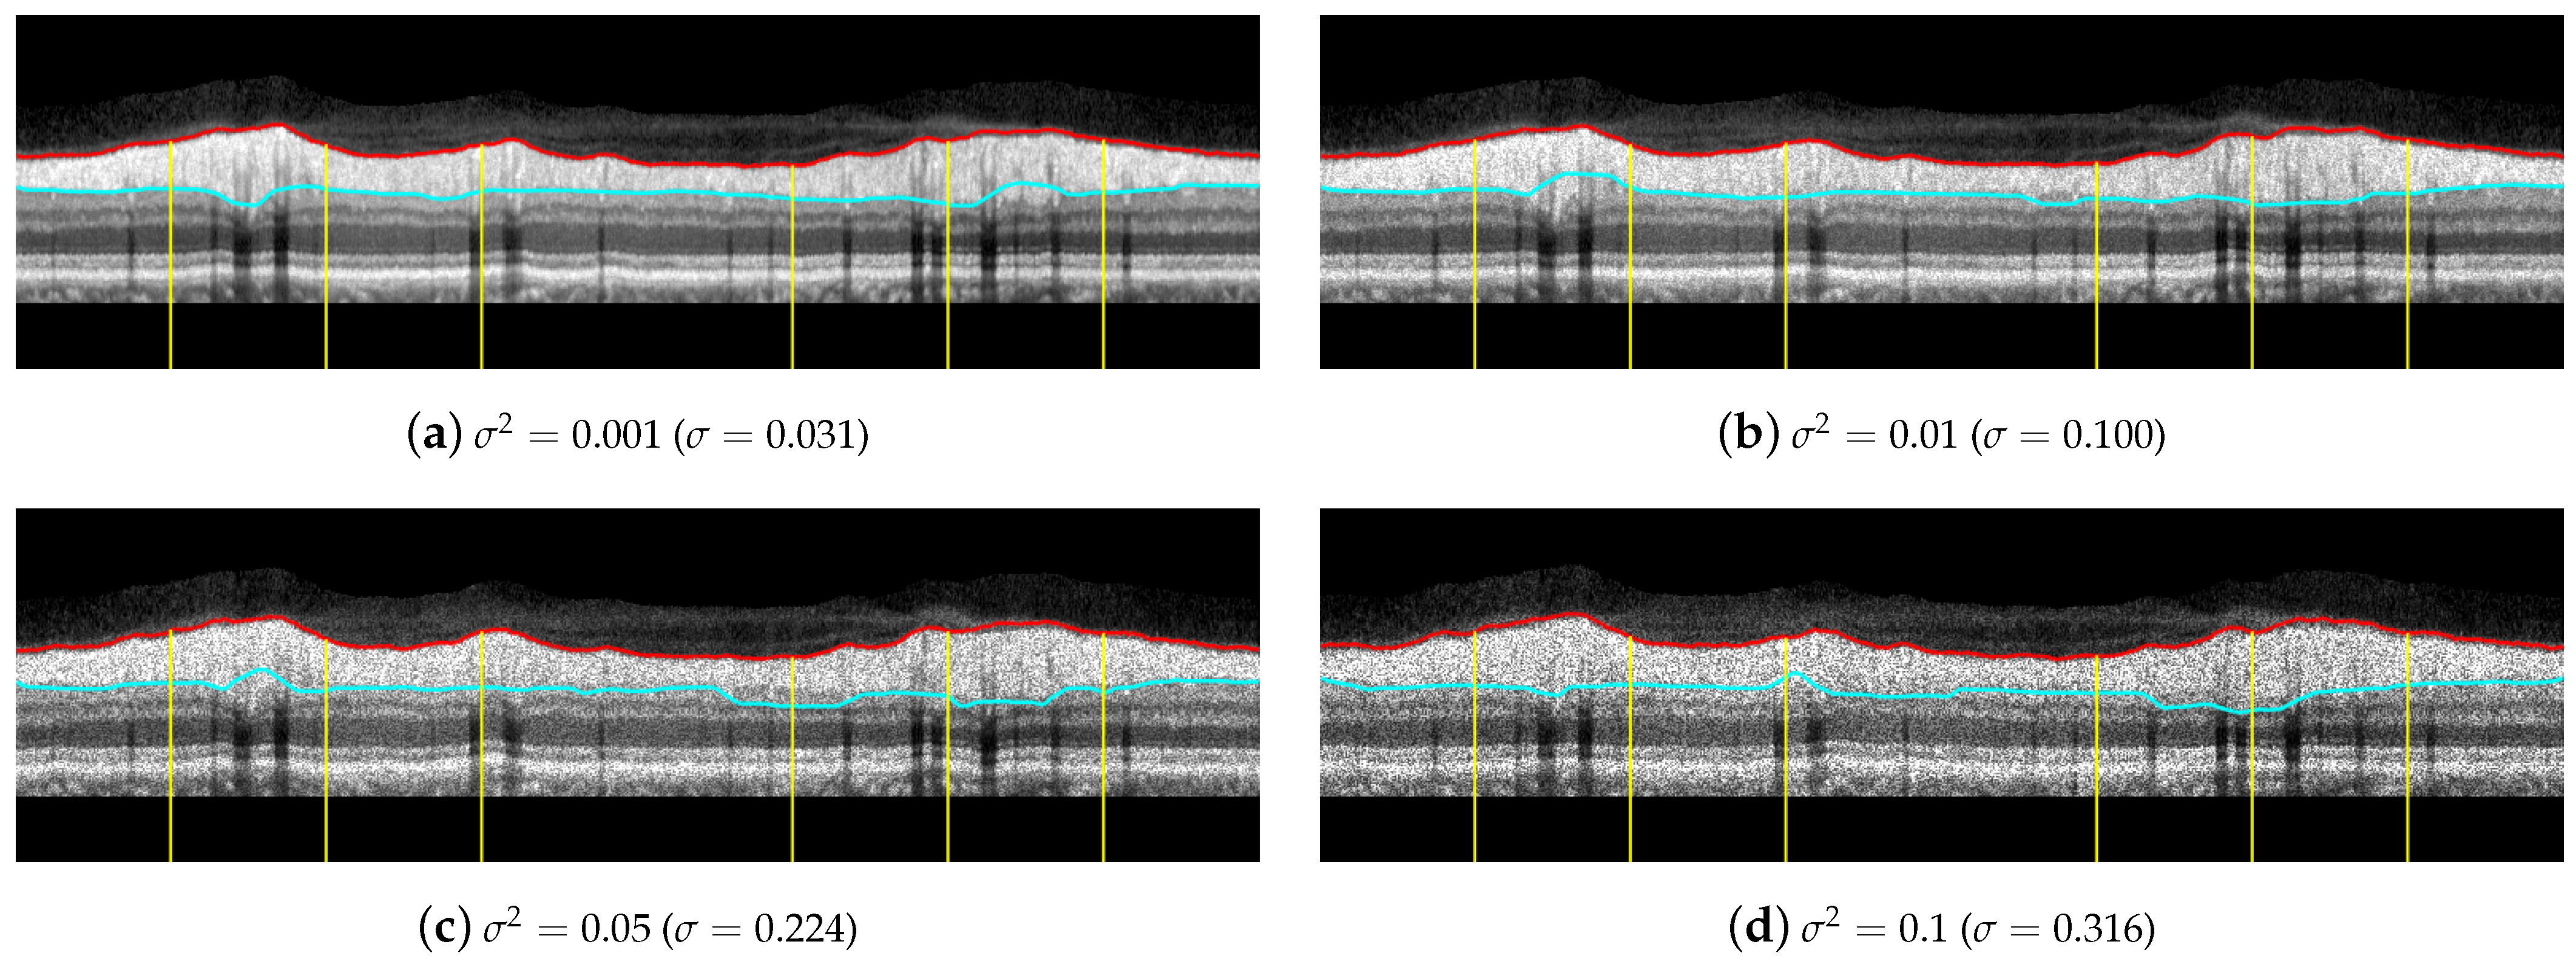

Regarding the influence of speckle noise on the results of the segmentation, it is negligible for most OCT images of the database due to their correct acquisition and their limited number of artifacts. Nevertheless, the bypassing of these filters could cause problems in OCT images with a higher level of noise or number of artifacts. The proposed filtering suppresses with morphological openings the typical bright spots of speckle noise in Equations (4), (10) and (23); and suppresses with morphological closings the dark spots in Equations (7) and (23). As indicated above, the parameter of this filtering, i.e., the size of the structuring element, is not critical, and there is a wide range of values in which the performance of the filtering is optimum. The mean value of the standard deviation of the speckle noise within the dataset used in this work is estimated using the NOLSE estimator [71], resulting in , within the range of = [0.0030–0.0292]. To evaluate the robustness to speckle noise of the proposed method, we tested the method over the OCT images with synthetically added speckle noise with standard deviation from to (variance from to ). Figure 18 illustrates the results on an image with a speckle noise estimation of . The performance of the method is appropriate with noise level below . As can be seen in Figure 18d, by exceeding this level, the #3-LB was not correctly detected, resulting in an incorrect adjustment to the CGL + IPL layer. It should be noted that given the visual degradation achieved in OCT images, this value should be outside of any realistic practical situation.

Figure 18.

Results of testing the robustness against synthetically incorporated speckle noise from to ( to ). The NOLSE estimation [71] of the speckle noise for the raw image is ().